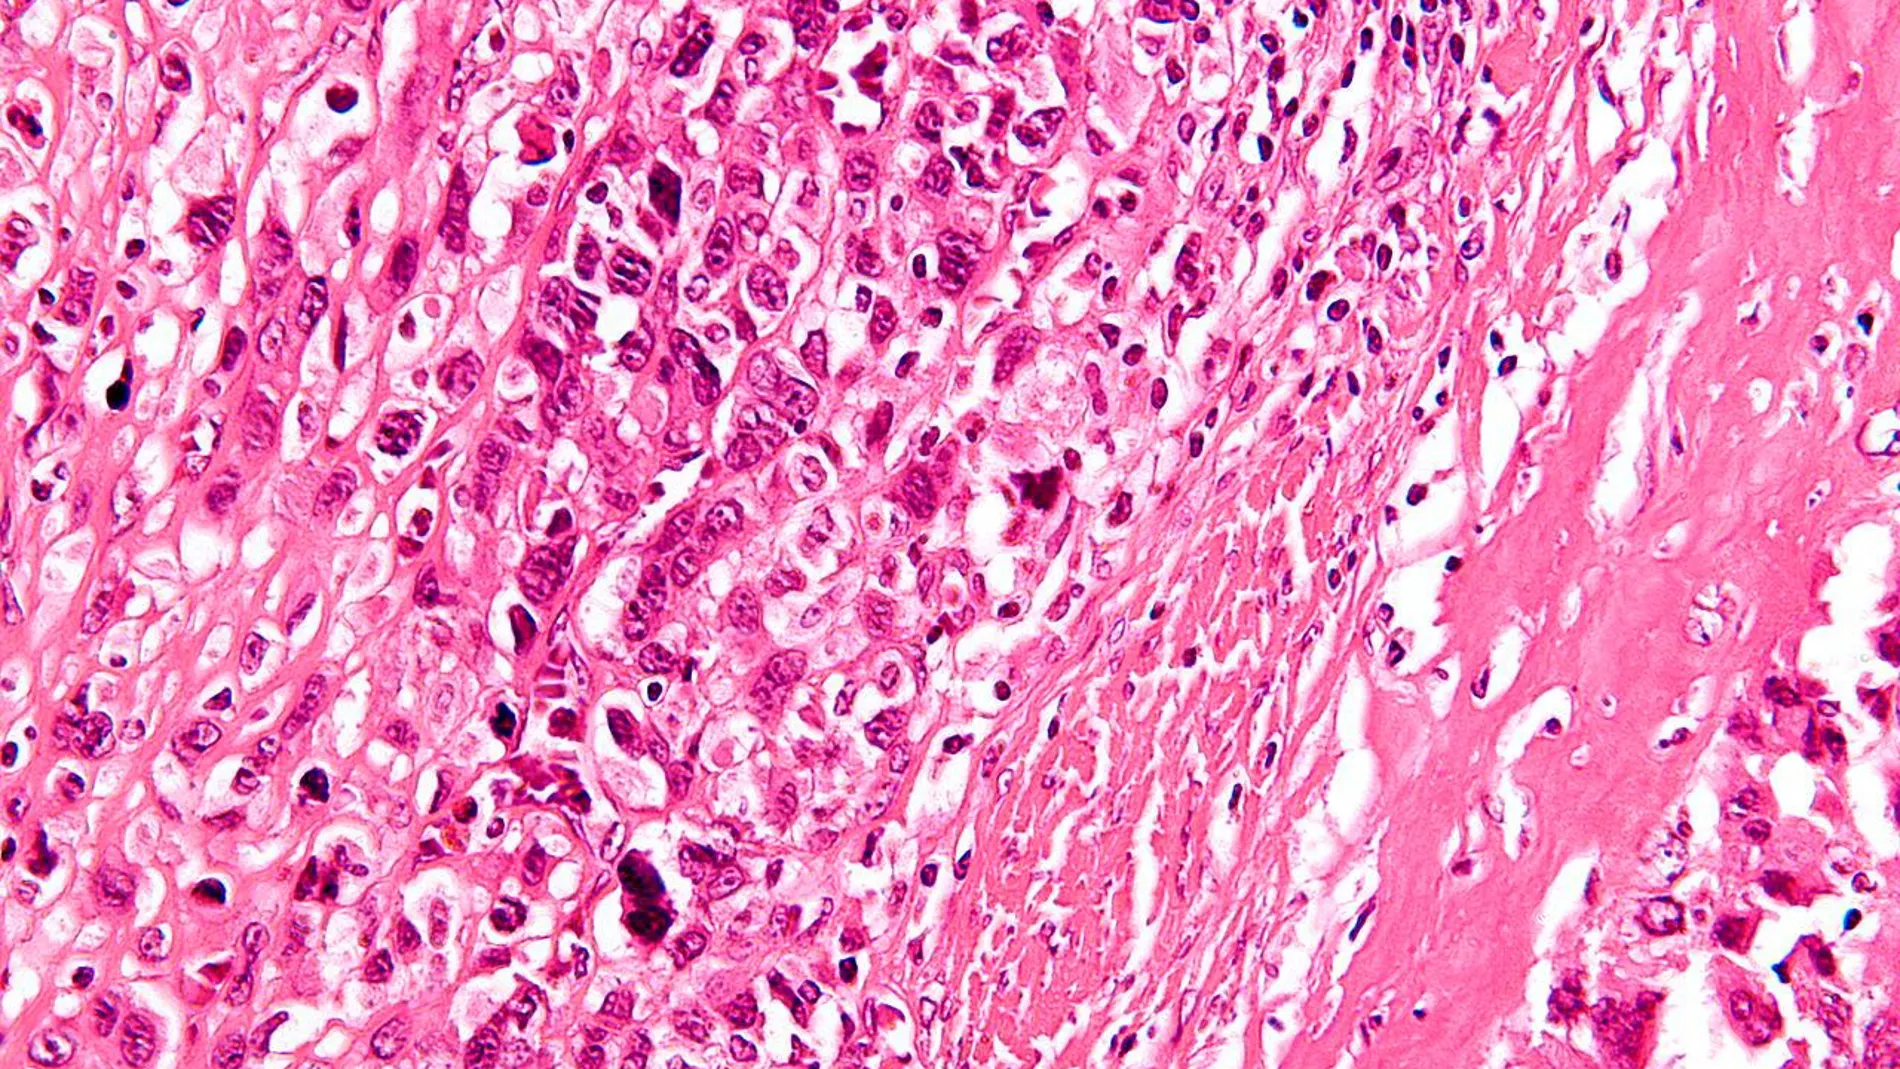

Así es un osteosarcoma, la enfermedad que sufría la hija de Luis Enrique

Xana, hija de Luis Enrique, ha fallecido este jueves a los nueve años de edad víctima de un osteosarcoma, el cáncer de huesos más común en los niños. Conocido también como sarcoma osteogénico, se trata del sexto tipo de enfermedad infantil más frecuente y representa alrededor del 3% de casos de cáncer pediátrico.

Es un tumor óseo maligno derivado de las células que generan el hueso. A pesar de que es una enfermedad muy poco frecuente, se diagnostican cuatro nuevos casos al año por cada millón de niños.